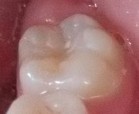

Bệnh nhân: Trần Nguyệt H. 7 tuổi, Răng 46, mã BA 11907/17

Sau sáu tháng. ICDAS: 1; Di: 15 | Sau chín tháng. ICDAS: 0; Di: 13 | Sau 18 tháng. ICDAS 0; Di:7 |